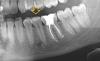

leoteo Опубликовано 26 мая, 2013 Поделиться Опубликовано 26 мая, 2013 Здравствуйте, уважаемые стоматологи! Очень нужна Ваша консультация. Около месяца назад на десне появилось белое пятнышко, похожее на прыщик или жировик. Никакого дискомфорта не доставляет. Жевать не больно, прикасаться тоже. Только языком чувствую этот прыщик. Зуб пломбирован - был контактный (щечный/боковой) кариес. Несколько месяцев назад начала пользоваться электрической зубной щеткой - может, это травматический стоматит? Спасибо за ответ.Прикладываю фото десны и рентген челюсти, который делала полгода назад. Ссылка на комментарий

1586Doc Опубликовано 26 мая, 2013 Поделиться Опубликовано 26 мая, 2013 Возможно требуется лечение 35 зуба. Советую сходить к стоматологу на осмотр. Ссылка на комментарий